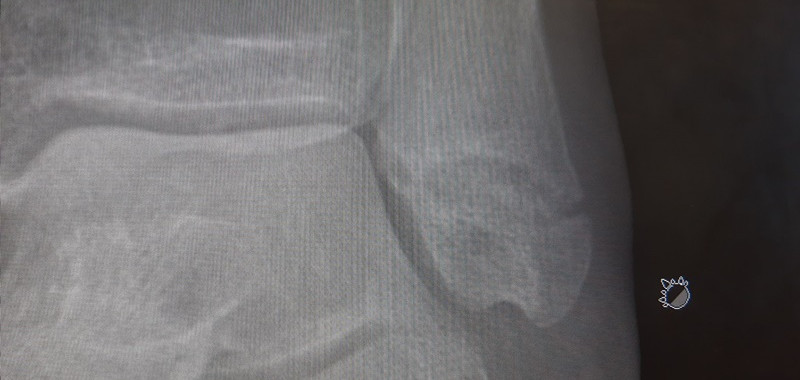

{A few days after they left , I finished off doing the deck and sealed it, so causing two huge knee blisters - oh joy THEN the next day - just to make my life more interesting , I was out playing 'chuckit' with the puppies and walkabout and I found a rabbit hole - 11 yrs of owning this ranch - ugh - first a sprain but after 2 weeks not healing I organized an X-ray and it's broken at the bottom of the Fibula - half an inch higer it would have been a complete break across and surgery with pins and plaster cast - so now a C3P0 boot for a month and leg up resting - ugh - hated that - then Xray on the 13th October - half way fused , so more boot time but just outside but I can now walk about and exercise it - next X-ray on Nov 19th but least I can get on the exercise bike and erase the atrophy}